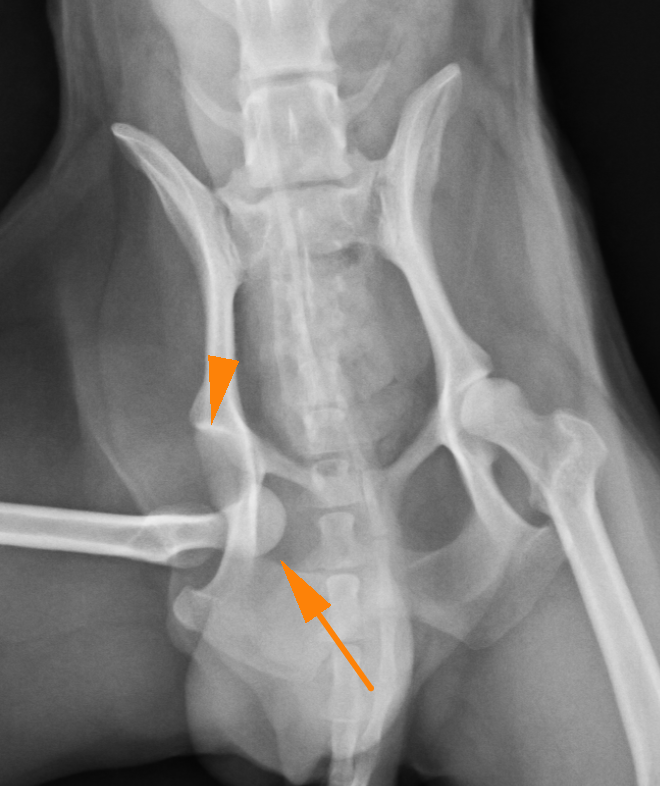

股関節脱臼

股関節とは骨盤の寛骨臼と呼ばれる凹みの部分に、大腿骨の大腿骨頭と呼ばれる球状の骨がはまることで関節しています。それが外傷や、寛骨臼の形成不全などによって抜けてしまうことを股関節脱臼といいます。

股関節が脱臼すると強い疼痛を引き起こし、足を地面に着けることができなくなり挙上してしまいます。股関節脱臼は脱臼する向きによって大きく2つに分けられます。90%が頭背側脱臼というもので、前方かつ、上方に脱臼してしまうタイプです。残りの10%が尾腹側脱臼というもので後方かつ、下方に脱臼してしまうタイプです。治療には用手による整復と、手術による治療がありますが、用手による整復の成功率は非常に低いとされており、基本的に手術によって整復します。頭背側脱臼ではワッシャーによる固定またはトグルピン法、骨頭切除などの術式が選択できます。症例によって治療法を選択しますが、可能であれば骨頭を切除せずに戻すのが理想と言えます。骨頭を切除すると術後の機能回復に時間がかかるのと、機能が元のの70〜80%にとどまると言われているからです。